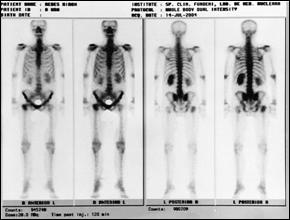

Cele mai multe metasteze la distanta, provocate de tumorile vezicale maligne, sunt localizate in plamani si in oase. Diagnosticul acestora se face prin: radiografii toraco-pulmonare, radiografii osoase sau scintigrame osoase (evidentiaza metastazele osoase cu 9-12 luni mai devreme decat expresia evidenta a acestora pe radiografiile standard).

4. Scintigrama osoasa

Cele mai multe metasteze la distanta, provocate de tumorile vezicale maligne, sunt localizate in plamani si in oase. Diagnosticul acestora se face prin: radiografii toraco-pulmonare, radiografii osoase sau scintigrame osoase (care evidentiaza metastazele osoase cu 9 - 12 luni mai devreme decat expresia evidenta a acestora pe radiografiile standard).

a. b.

Figura 48. a,b) Scintigrafii osoase la un bolanavi cu tumori vezicale si metastaze osoase multiple.